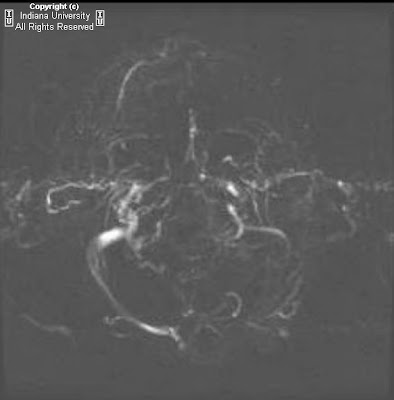

Figure 6: Axial FLAIR image the level of the anterior commisure. Bilateral, well-circumscribed areas of FLAIR high signal intensity localize to the corticospinal tracts are demonstrated.

Typical MR imaging findings include high signal intensity involving the corticospinal tracts on T2, FLAIR and proton density weighted imaging. This abnormal signal intensity may be seen extending from the hemispheric white matter, through the corona radiata, through the caudal aspect of the posterior limbs of the internal capsules, and finally into the ventral aspect of the brain stem. The signal abnormality appears symmetric and well circumscribed. Occasionally signal abnormality is seen extending into the anterolateral column of the spinal cord. Involvement of the corpus callosum has also been reported.

Care should be taken when evaluating the corticospinal tracts on T2-weighted images because about 50% of normal patients display symmetric foci of high signal intensity that are isointense to gray matter on T2-weighted images within the caudal one-third of the posterior limbs of the internal capsules. However, in normal patients, the signal should never extend above the internal capsule to the corona radiata. Proton density imaging is more specific in evaluating for abnormal signal since in normal patients, the corticospinal tracts are isointense to the remainder of the internal capsule and therefore any abnormal signal on PD should be considered pathological.